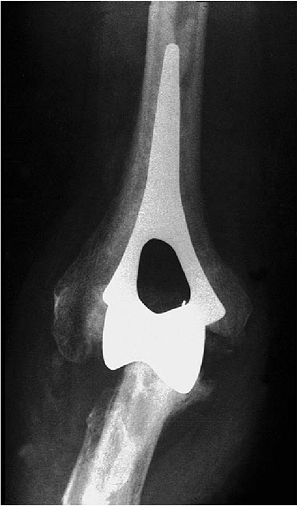

![]() |

|

Figure 17-27. A,B:

Patient with significant bone deterioration but adequate stock and collateral ligaments for the minimally constrained Kudo implant. |

Figure 17-28. A,B:

Two years after implantation with methylmethacrylate, the patient has functional motion and no pain, and there is no evidence of implant loosening. |